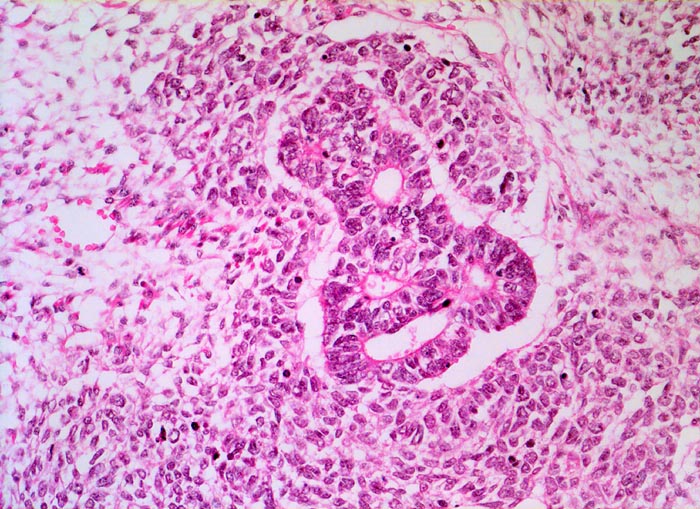

Wilms-Tumor

Komplexe kribriforme epitheliale Strukturen innerhalb des zellreichen Blastems.

Graubrauner scharf begrenzter weicher Tumor mit fokalen Nekrosen und Einblutungen.

Palpabler Tumor im linken Hemiabdomen. Makrohämaturieepisode.

Histologie

200